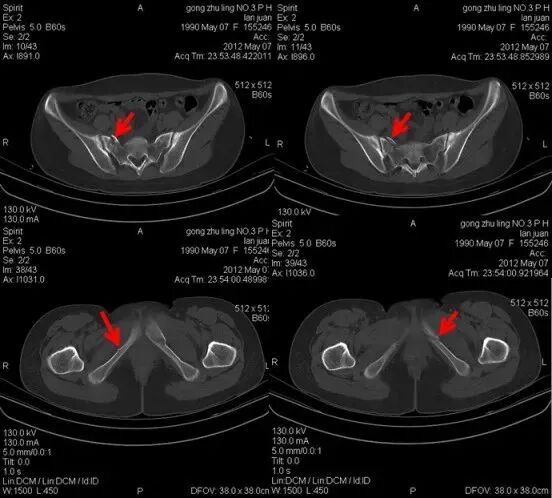

2012年3月22日片子

同一患者2012年7月15日片子